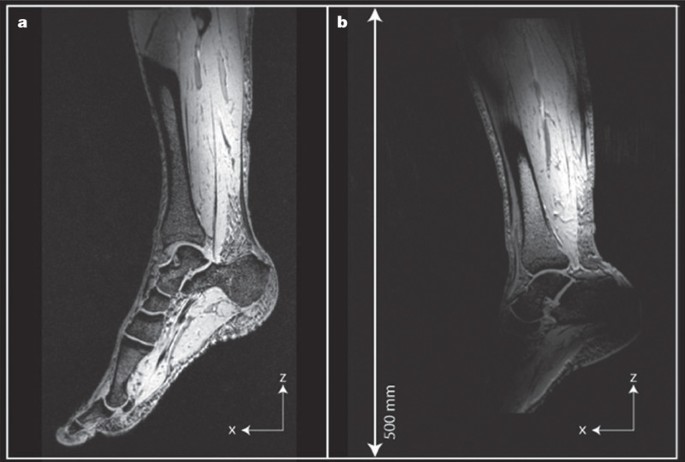

Mri Scan London Sports Orthopaedics

A Baseline Diagnostic Mri Of Active Stage Charcot Foot Grade 0 Four Download Scientific Diagram

Mri Of Left Ankle Axial Proton Density Spectral Presaturation Download Scientific Diagram